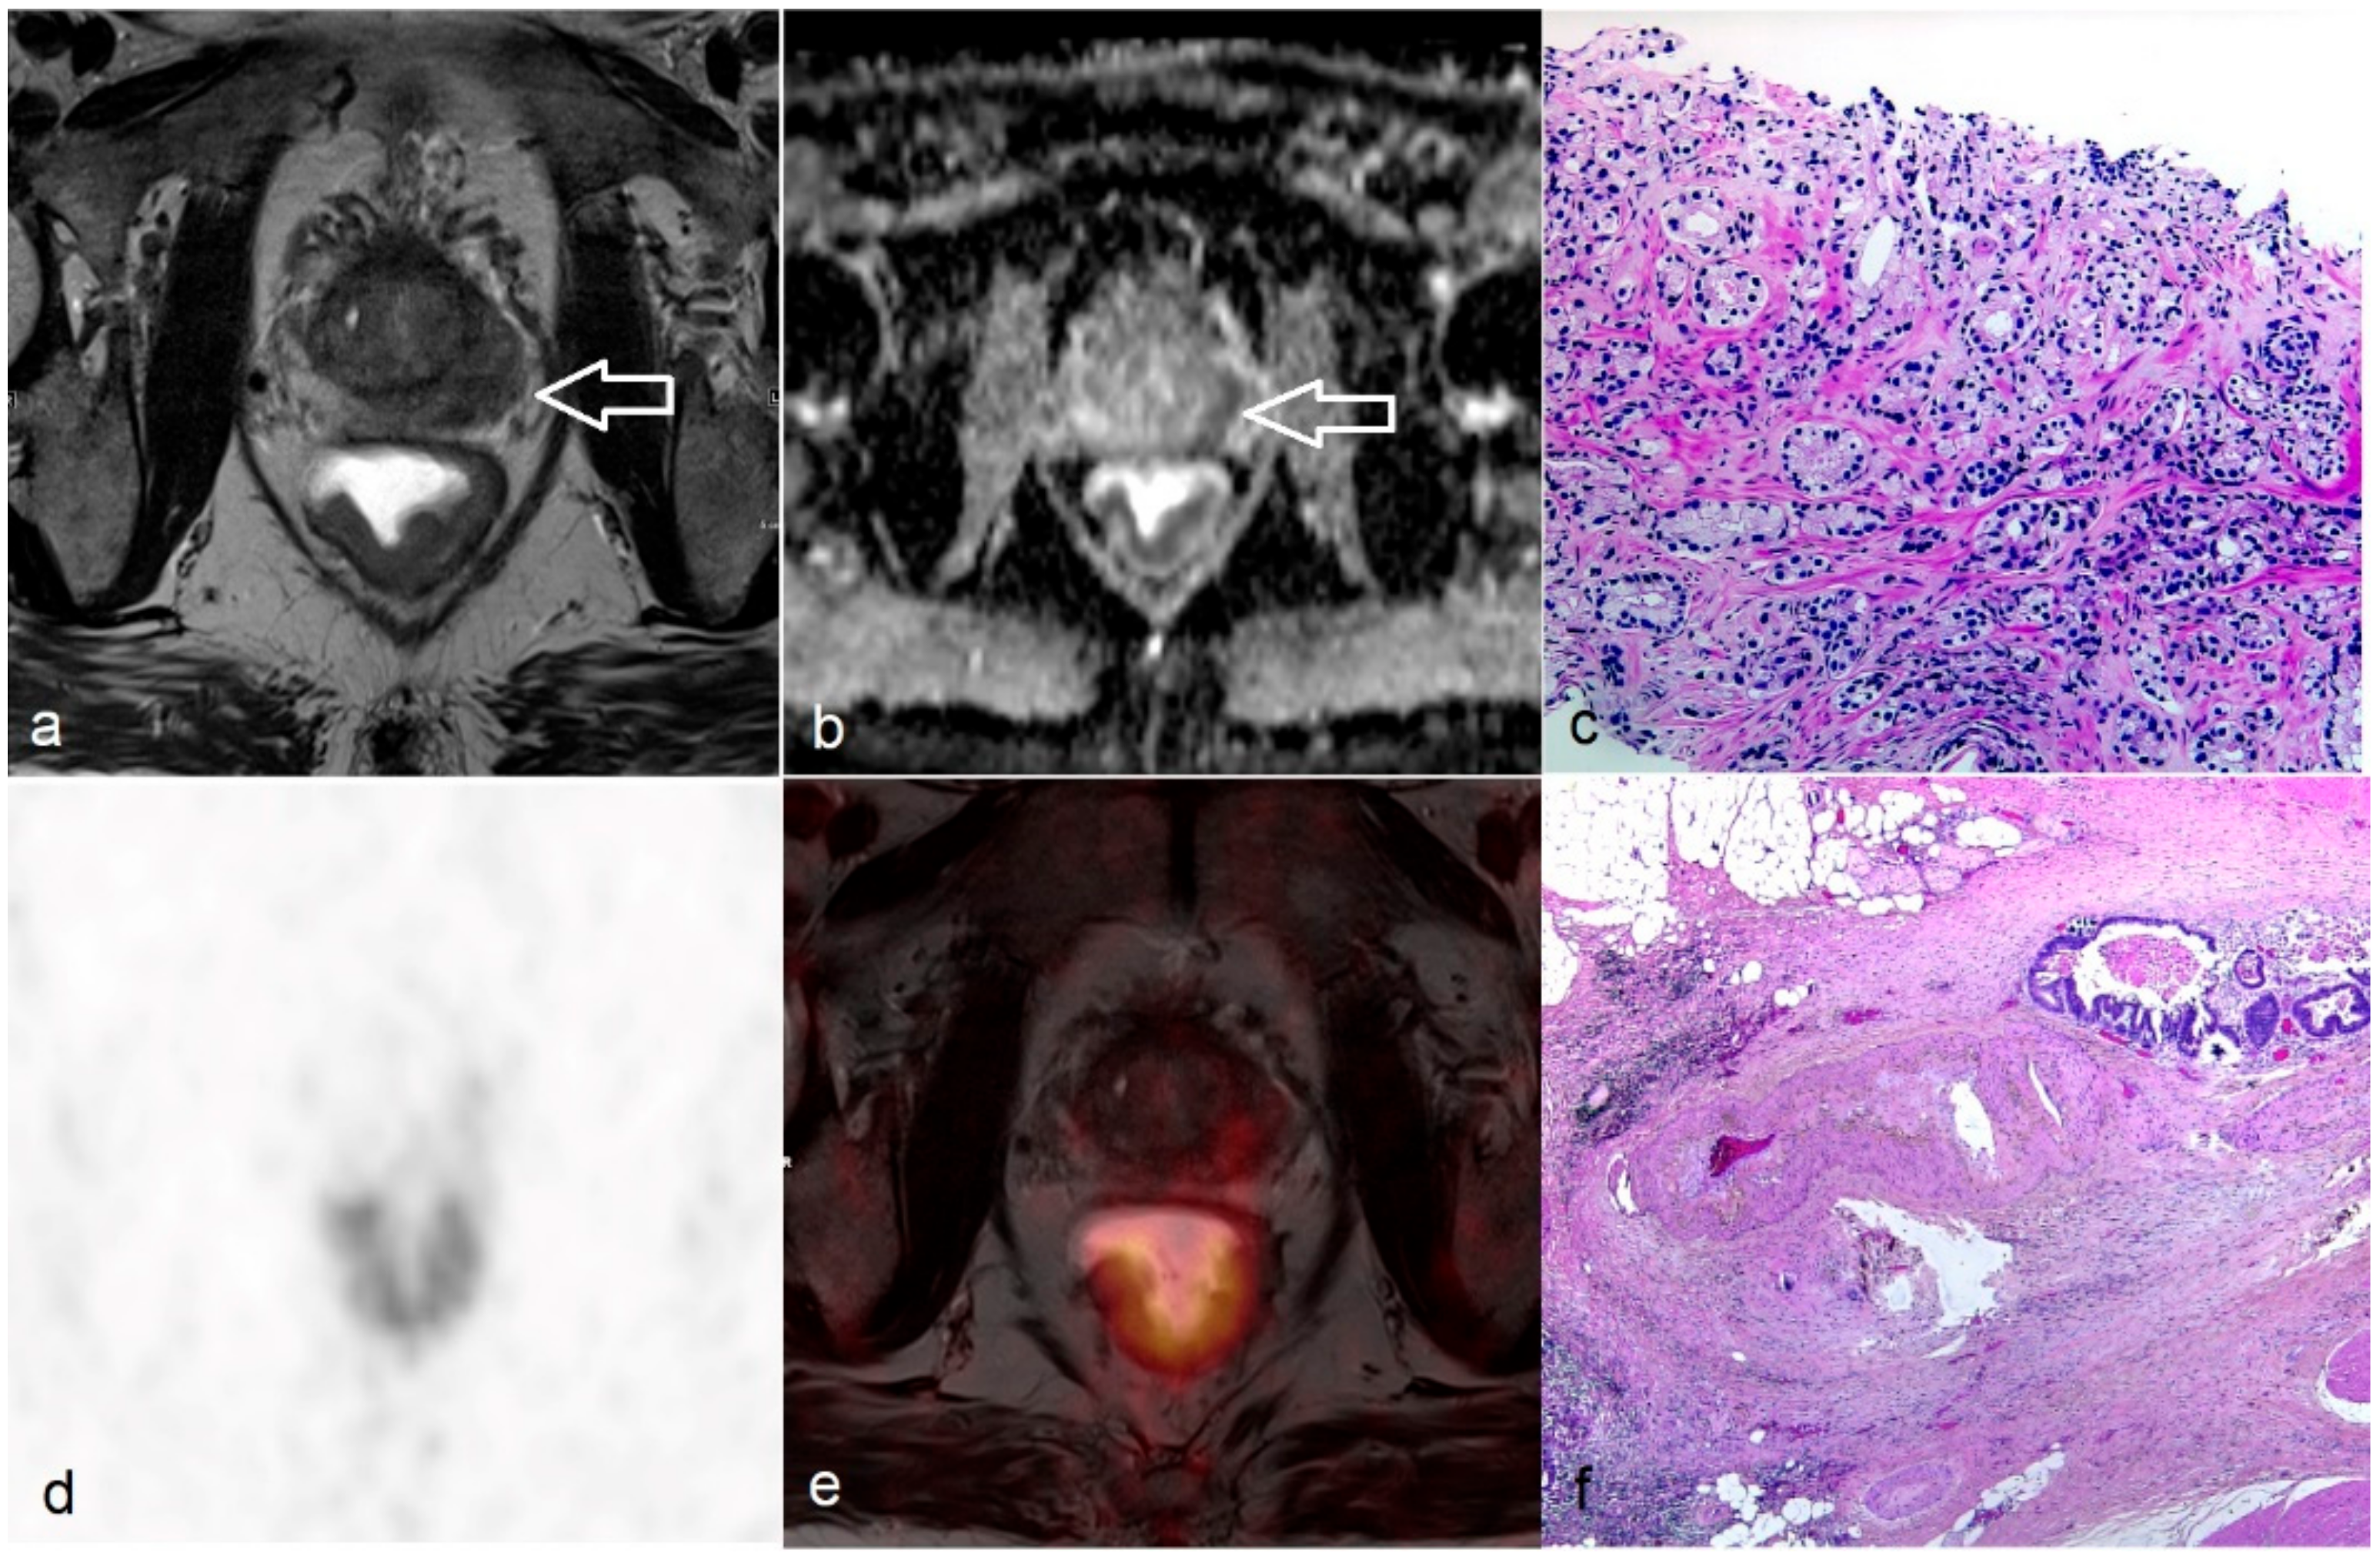

3.4. Metabolic Information of Untreated and Post-CRT Rectal Tumor